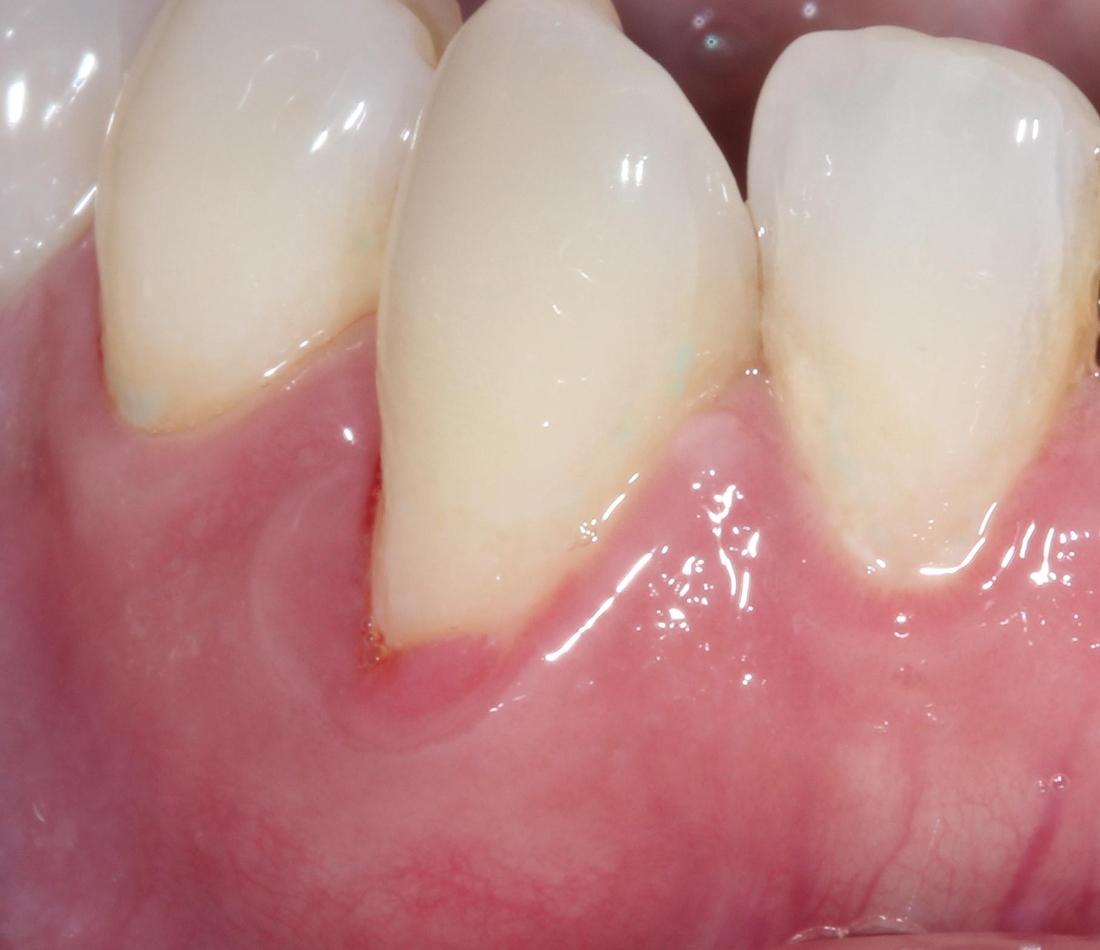

After: 1 month after deep cleaning, the inflammation and swelling resolved.